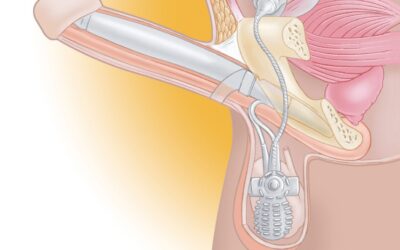

La dysfonction érectile

et sa prise en charge par des implants péniens gonflables.